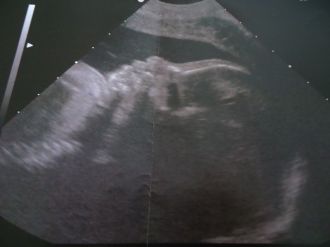

Rendez vous aujourd’hui hui j'ai le gynéco a 11 h en espèrent cette fois si connaitre le sexe du bébé et ouii..

C'est un garçon nous somme très heureux , il pèse 510 g et il est en très bonne forme :)